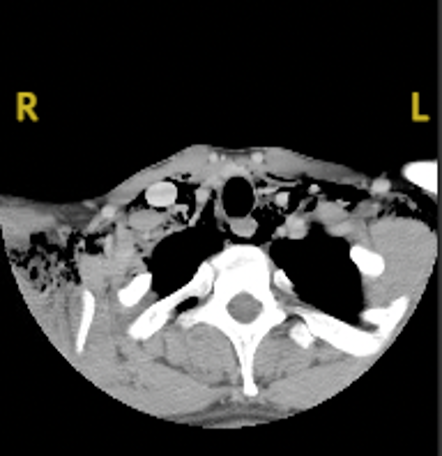

Diagnostic testing. The patient’s white cell count was 12.04 (normal range, 3.50-10.80) and his creatinine was 2.70 (normal range, 0.7-1.2). Although no alcohol was detected in his blood sample, a drug screening was positive for amphetamines and cannabinoids. His respiratory viral panel was negative, and his rapid step was positive. The oral ulcer was cultured as well. Due to his trouble swallowing, a chest x-ray was obtained (Figure 1), which showed pneumomediastinum. The patient’s chest and neck computed tomography (CT) showed moderate pneumomediastinum (Figure 2) and extensive subcutaneous emphysema within the base of the neck (Figure 3).

Fig. 2. The patient’s neck CT with contrast is shown.